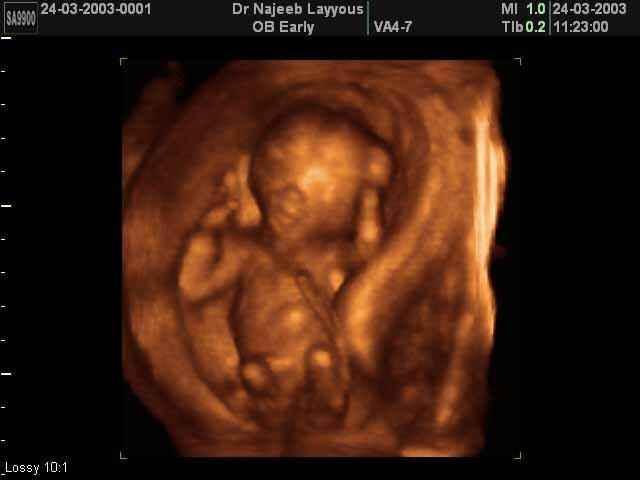

- 3D Photos Ecographie du Premier Trimestre

3D Photos Ecographie du Premier Trimestre (Photos d’échographie de tôt grossesse)| Dr N Layyous